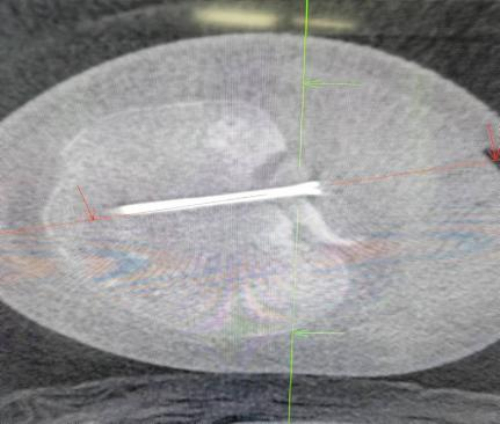

术中操作